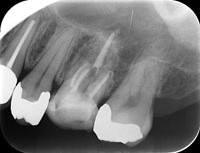

• 根管充填

レントゲン画像

可能な限り根の細菌を減らした後、根管充填材を根に緊密に充填し、細菌が増殖し得るスペースを無くします。